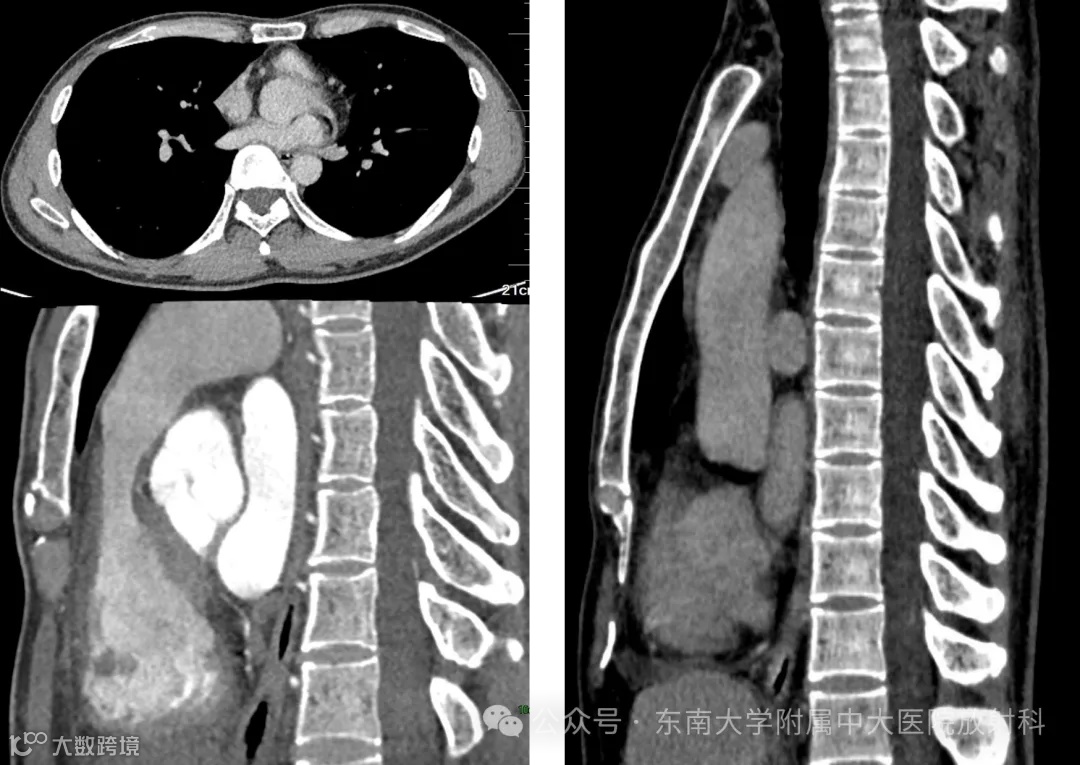

病例1

性别:女 年龄:53岁

主诉:心前区不适半年

现病史:患者半年前无明显诱因下出现心前区胀痛,伴胸闷气促,无双下肢水肿,服用硝酸甘油无明显缓解,现服用中药治疗,无咯血,无头晕晕厥,无寒战发热,无恶心呕吐。2025-01-12查心脏彩超示:二尖瓣前、后叶脱垂致二尖瓣中度返流,不除外Barlow 综合征可能;左房轻大,三尖瓣轻度返流, 左心功能正常

既往史:既往身体一般,高血脂病史2年,腔隙性脑梗塞病史1年;2015年行乳腺结节切除术,2017年行胆囊切除术,具体不详

专科检查:心尖搏动位置位于第五肋间左锁骨中线外侧 0.5cm,心浊音界扩大,律齐,心尖区可闻及3/6级收缩期杂音

实验室检查:心梗定量测定

影像: 2025-07-08 胸部CT增强+冠脉CTA+颅脑、腹部平扫

影像学表现